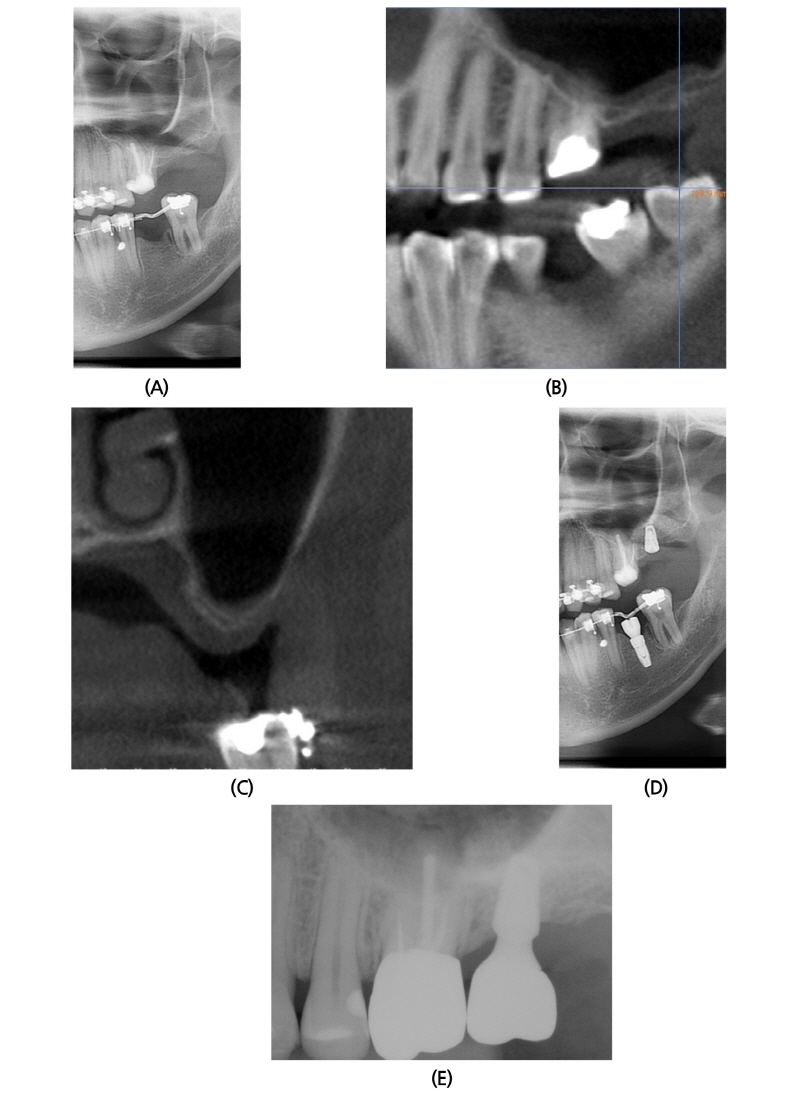

2014년 10월 21일 37세 여성이 교정치료 중 임플란트 식립을 원한다는 주소로 본과 내원하였다. 환자는 특기할 내과적 기왕력이 없었고, 본과 내원 시 #27 missing 상태였다(Fig. 4A). 수술 전 촬영한 CBCT 소견상, #27 부위 상악동저의 높이는 1.5~2.0 mm 정도였으며, 상악동 내부는 sinusitis 소견없이 깨끗했다(Fig. 4B, 4C). 2014년 12월 9일 #27 부위에 상악동 골이식과 임플란트 동시 식립술을 시행하였다(Fig. 4D). 골이식재로 ICB® 1.0g과 MBCP® 0.25g을 혼합하여 사용하였으며, Bone window를 opening 하면서 채취한 cortical bone을 다시 덮어주었다. 차단막은 사용하지 않았다. #27 부위 Implantium® (Ø4.3 × 8 mm, drilling Ø3.4 mm) 식립하였다. 수술 후 2년 6개월 후에도 임상적, 방사선학적으로 양호한 상태를 보이고 있다(Fig. 4E).